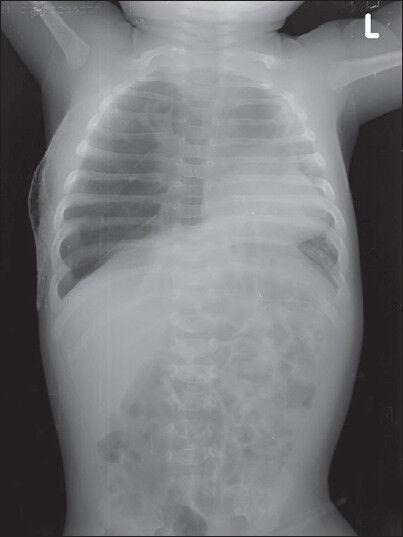

Congenital lobar emphysema (CLE) is a rare congenital anomaly of lung causing over aeration of one or more lobes of a histologically normal lung. It presents in infancy with respiratory distress due to compression atelectasis and often associated with mediastinal shift and hypotension. CLE poses a challenge in diagnosis and positive pressure ventilation due to air trapping. We report a case of 8-week-old infant with CLE posted for right lobectomy. Strategies to prevent misdiagnosis, over aeration and use of IPPV have been reviewed.

先天性肺叶气肿(CLE)是一种罕见的先天性肺部异常,可导致组织学正常的一个或多个肺叶过度充气。它在婴儿期因压迫性肺不张而出现呼吸窘迫,常伴有纵隔移位和低血压。由于气体潴留,CLE在诊断和正压通气方面构成挑战。我们报告一例8周大患有CLE的婴儿拟行右肺叶切除术。已对预防误诊、过度充气和使用间歇正压通气的策略进行了综述。